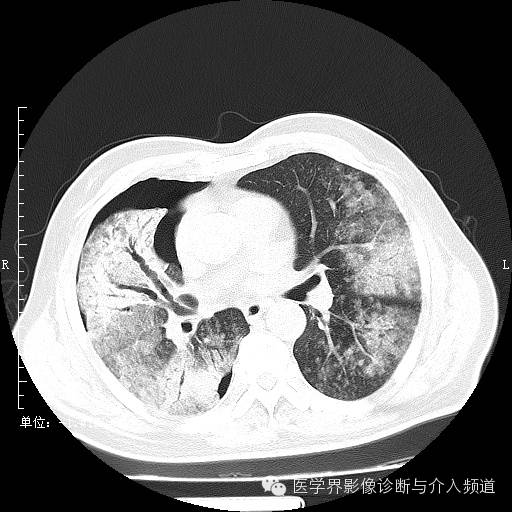

初诊

初诊:右肺上叶见大片实变影,呈磨玻璃状及网状,可见“充气支气管征”,纵隔窗可见实变影范围有所缩小,呈蜂窝状,局部支气管走行不自然,管壁不光滑。